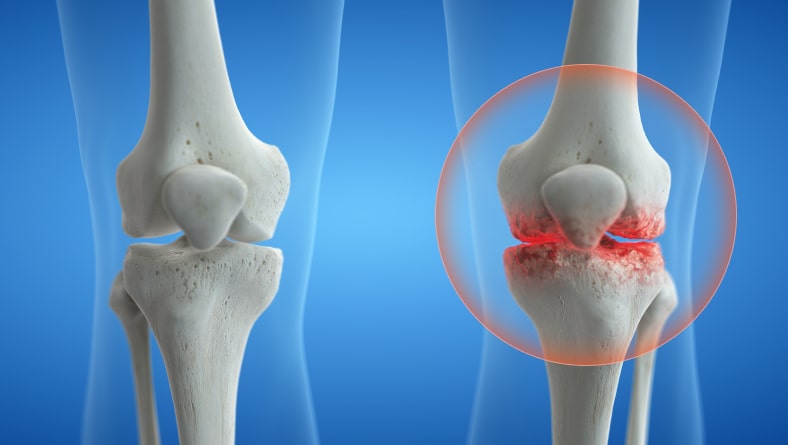

Qualsiasi di questi segni indica un danno

La struttura dell'articolazione tra le ossa è una struttura complessa. È costituita da una membrana con uno speciale liquido lubrificante (liquido sinoviale), dalla cartilagine e dai tessuti periarticolari. I neuroni presenti nei tessuti inviano segnali di dolore in caso di problemi all'articolazione.

gonartrosi

Deformazione e distruzione della cartilagine a causa dell'infiammazione.